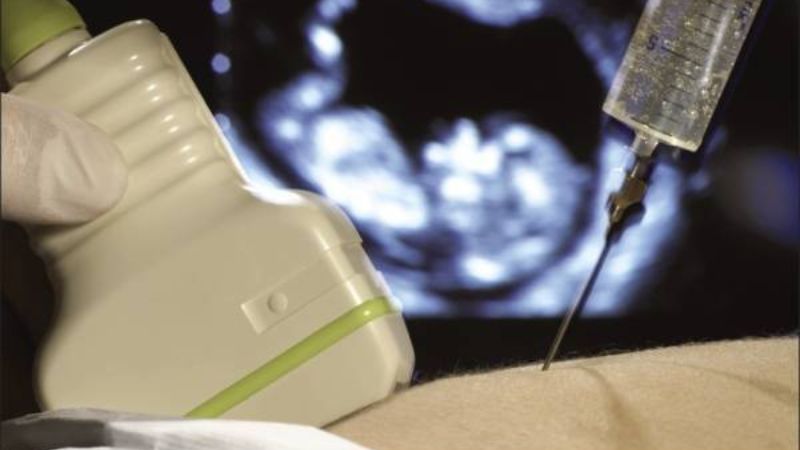

Phương pháp xét nghiệm xâm lấn sử dụng mẫu nước ối hoặc tế bào nhau thai để tiến hành phân tích. Trong trường hợp này, cần sự hỗ trợ của bác sĩ chuyên khoa để thu thập mẫu xét nghiệm một cách an toàn và giảm thiểu nguy cơ cho thai nhi. Thường thì mẫu nước ối được ưa chuộng hơn so với tế bào nhau thai để xét nghiệm, do trong nước ối chứa tế bào ADN của thai nhi. Sau khi thu thập mẫu nước ối, nó sẽ được chuyển đến phòng xét nghiệm và tiến hành các bước tách chiết và phân tích.

Phương pháp xâm lấn này thường được thực hiện khi thai nhi đã phát triển đến 16 tuần tuổi. Tuy nhiên, cần lưu ý rằng mọi xâm lấn đều đi kèm với nguy cơ tiềm ẩn. Xấp xỉ 1 trường hợp rủi ro xảy ra cho mỗi 500 thai phụ thực hiện phương pháp xâm lấn như chọc ối xét nghiệm ADN hoặc sinh thiết nhau thai, bao gồm nguy cơ rò ối, nhiễm trùng tử cung, sinh non sớm, hoặc thậm chí sảy thai (tương đương tỷ lệ 0,2%). Do đó, trước khi quyết định thực hiện xét nghiệm xâm lấn, thai phụ và gia đình cần tham khảo ý kiến các bác sĩ chuyên khoa để đưa ra quyết định phù hợp nhất.